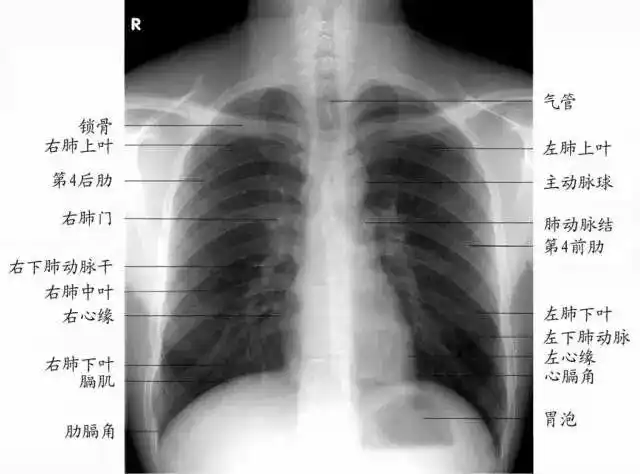

正常胸部正位片